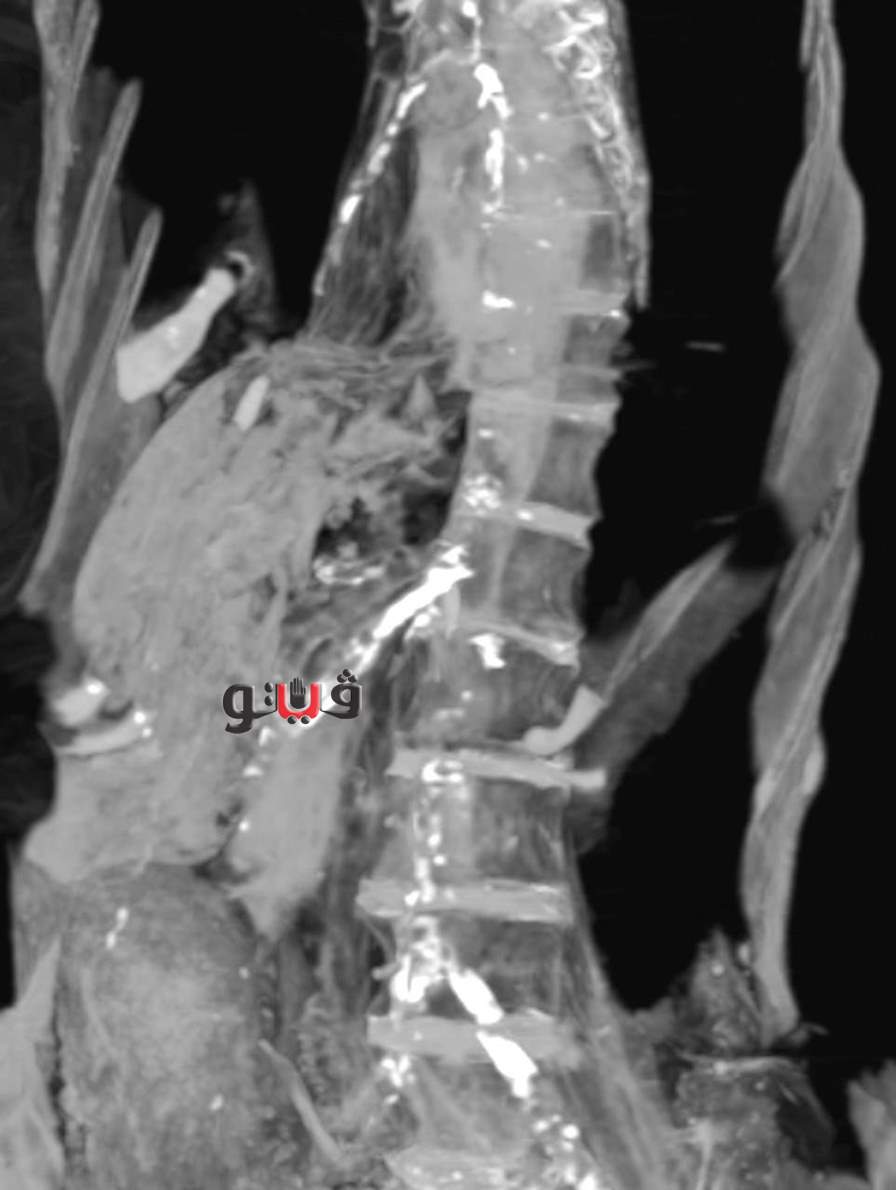

فأثبت فحص الأشعة المقطعية لـ ”مومياء المرأة غير المعروفه إىه” أنها عانت من تصلب في شرايين القلب التاجية الأيمن والأيسر وكذلك شرايين الرقبة وشريان الأبهر البطني والحرقفي، وكذلك شرايين الطرفيين السفليين والساقين.